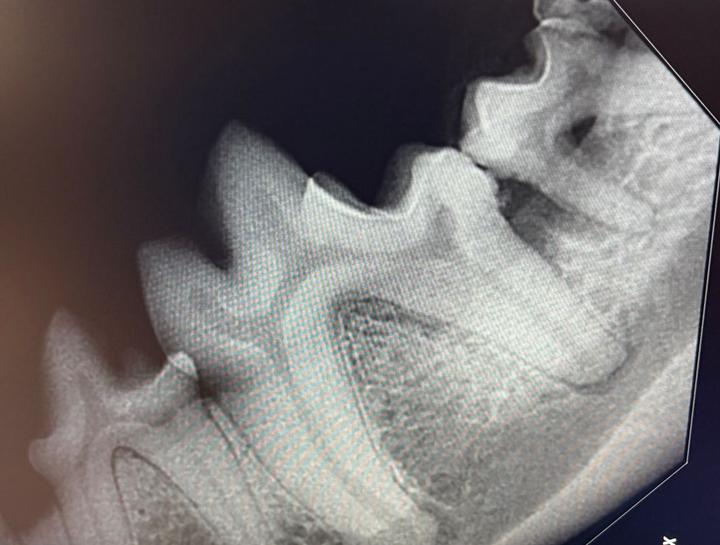

Digital Dental Radiology

Insight into underlying issues.